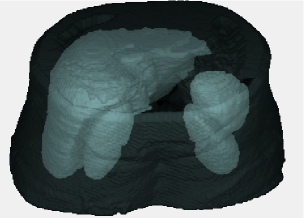

Figure 2 shows multi-object 3D ASMs for abdominal organs. Note that skins are also considered in the MA𝑀𝐴MAs to restrict the search space. Note also that mean shapes of the objects do not have any overlapped region with other mean shapes of the objects. Because, in training part, we select the objects Oisubscript𝑂𝑖O_{i} such that (OiOj)(ij)1,,M=subscriptsubscript𝑂𝑖subscript𝑂𝑗𝑖𝑗1𝑀(O_{i}\cap O_{j})_{(i\neq j)\in 1,\ldots,M}=\emptyset, implying that there is no overlaps across the objects. This fact leads to (𝐱¯𝐢𝐱¯𝐣)(ij)1,,M=subscriptsubscript¯𝐱𝐢subscript¯𝐱𝐣𝑖𝑗1𝑀(\mathbf{\overline{x}_{i}}\cap\mathbf{\overline{x}_{j}})_{(i\neq j)\in 1,\ldots,M}=\emptyset, as each mean shape 𝐱¯𝐢subscript¯𝐱𝐢\mathbf{\overline{x}_{i}} is created independently and alignment of the shapes of objects does not affect the distribution of objects in the mean shape due to the nature of the 7-parameter affine transformation A𝐴A: (OiOj)(ij)1,,M=(A(Oi)A(Oj))(ij)1,,M=(A(𝐱¯𝐢)A(𝐱¯𝐣))(ij)1,,M=subscriptsubscript𝑂𝑖subscript𝑂𝑗𝑖𝑗1𝑀subscript𝐴subscript𝑂𝑖𝐴subscript𝑂𝑗𝑖𝑗1𝑀subscript𝐴subscript¯𝐱𝐢𝐴subscript¯𝐱𝐣𝑖𝑗1𝑀(O_{i}\cap O_{j})_{(i\neq j)\in 1,\ldots,M}=\emptyset\Leftrightarrow(A(O_{i})\cap A(O_{j}))_{(i\neq j)\in 1,\ldots,M}=\emptyset\Leftrightarrow(A(\mathbf{\overline{x}_{i}})\cap A(\mathbf{\overline{x}_{j}}))_{(i\neq j)\in 1,\ldots,M}=\emptyset. Objects are not aligned individually, hence, their spatial relations before and after alignment does not change.

Figure 2. Mean shape is generated using 3D ASM for multiple objects of abdominal region. Left: Figure includes mean shapes of liver, spleen, right and left kidneys. Right: Figure includes mean shape of skin boundary of the abdominal region as well.